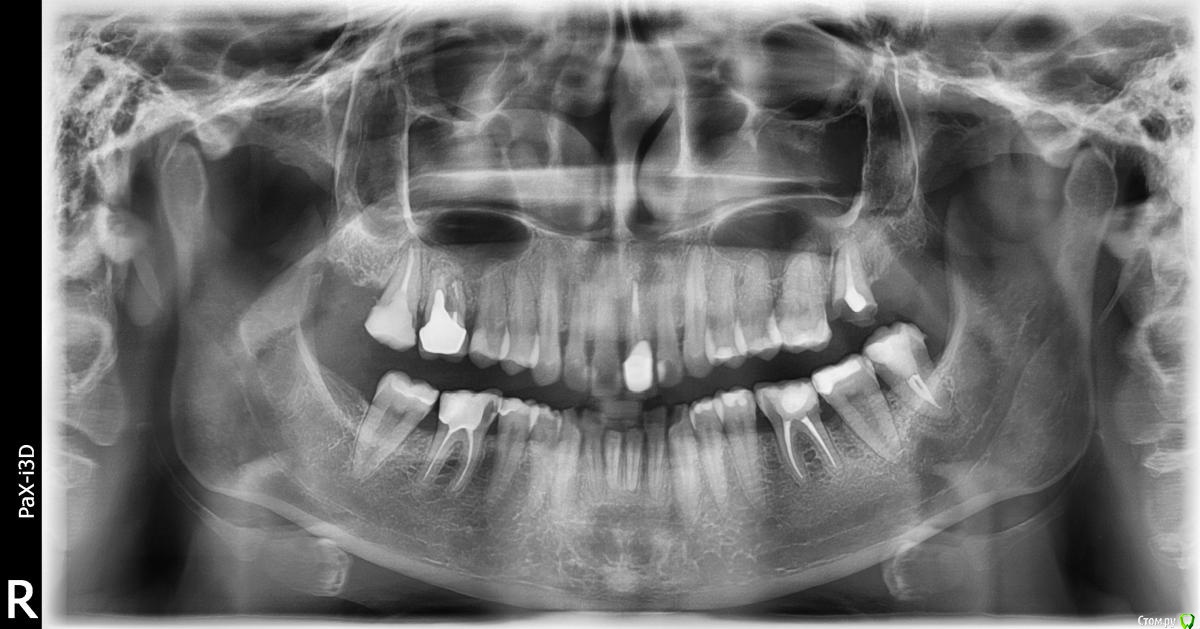

l_yulia Опубликовано 21 июля, 2015 Поделиться Опубликовано 21 июля, 2015 С этим зубом долгая история. 7 лет назад у меня там была киста и одновременно беременность, а когда беременность закончилась, а киста была вылечена, то в оставшийся корень вставили стекловолоконный штифт и на него коронку. Коронка металлокерамическая, врач мне сказала тогда, что поставить безметалловую керамику нельзя (видимо им просто почему-то так было удобнее). Коронка была толще чем мой собственный зуб и именно это стало причиной того что в конце-концов коронка вместе со штифтом вывалилась (я ее как бы все время толкала нижними зубами).Так как финансовой возможности в момент выпадения коронки никакой не было от слова совсем, то я решила приклеивать его каждый день на корегу, и регуляно полоскать антисептиками. Но на прошлой неделе, когда я ела персик, коронка внезапно отклеилась, а я не сразу заметала и продолжила кусать персик, потом услышала хруст и поняла, что придется уже решать как-то проблему. Скорее всего я все таки сломала корень, так как потом 2 дня были не очень приятные ощущения в области зуба.В прошлую пятницу и субботу я записалась в 3 стоматологических клиники на консультацию на счет имплантации. Я хотела одномоментную с удалением корня имплантацию, и желательно чтоб можно было сразу установить временную коронку, так как зуб передний.И вот что мне сказали в разных местах:1) Сказали, что да, можно поставить сразу. В той клинике используют только 2 системы имплантов ("Implantium" и "SuperLine"). И они мне посчитали "SuperLine". Правда сказали, что о том возможно ли будет нагружать имплант сразу станет понятно только после удаления, глядя на состояние кости, плотная она или рыхлая. И еще сказали, что обязательно потребуется пересадка кусочка кожи с неба на десну. 2) Здесь ставят разные системы ( "Miss", "Alpha bio", "AstraTech", "Implantium" и "SuperLine"). Я сказала, что думала про alpha bio и мне посчитали его, но потом врач мне аргументированно объяснил, что чтоб имплант можно было сразу нагружать он должен быть длинее собственного корня зуба, а этому требованию соответствует только "SuperLine" и что потребуется подсыпка костной ткани. И он не возражал против временной коронки и был категорически против протеза бабочки, мол он все сосочки примнет.3) Здесь ставят разные системы ( AlphaBio и MIS, Xive и Impro, Straumann, Nobel Biocare и Biohorizons, Astra Tech) Врач сказал мне, что нет никакой разницы какой длины сам имплант и посчитал мне MIS. Напугал меня тем, что при удалении оставшегося корня зуба у меня не останется передней стенки (если поставить имплант одномоментно, то он будет просвечивать) и лучше будет, если сначала удалить зуб, а имплант поставить через 2 недели, когда кровяной сгусток видоизменится в костную ткань. Он был категорически против сразу ставить временную коронку и был за протез бабочку, когда я спросила про сосочки, то он сказал, что мы так сделаем протез, что ничего не примнем.А теперь мне хочется здесь на форуме получить независимую консультацию и понять, какой имплант лучше, действительно ли он должен быть длинее собственного корня или это не имеет никакого значения?Правда ли что у меня после удаления не останется переднней стенки кости?Кто из врачей, которые меня консультировали , более компетентный? КТ у меня есть. Прикрепляю 2 снимка, может на втором что-то лучше видно. один 17.07.2015, а второй примерно полугодовой давности. И фото.17.07.2015 конец 2014фото Ссылка на комментарий